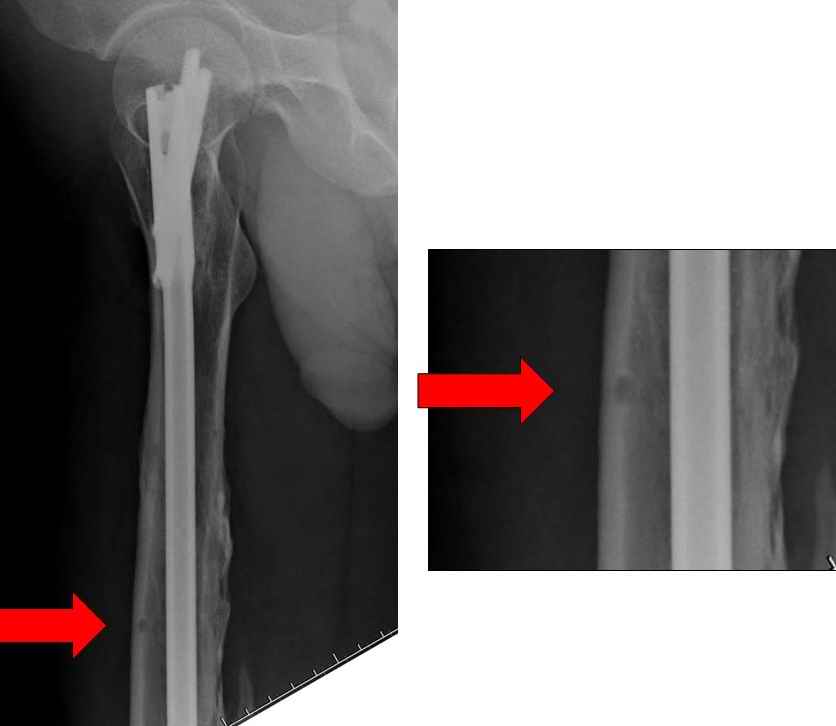

>“На представленных R-граммах нет снимков с АВФ. На снимке №4

>дистальный статический винт не доходит до второго кортикала “

Снимок №4 сделан после несостоятельности интрамедуллярного штифта, осложнения инфекцией канала и после миграции шурупов. Я имел ввиду, что снимок № 2 после удаления наружного фиксатора в интрамедуллярном варианте, на увеличенном снимке дырка на переднем кортексе (см. снимок) stress zone Чтобы правильно без осложнений провести half pins, необходимо соблюсти нескольких правил, во первых, они должны вводится в середине диаметра кости с предварительным просверливанием. Во время просверливания кости, сверло проходит первый, потом второй дальний кортекс и стержен вводится вручную. А иногда сверление проходит по касательной к кортексу, нагреваются местные ткани, создается ожог и локальный некроз. Или как будто делается кортикотомия с помощью сверла, как при

методе Илизарова, ослабляя кортикальный слой. Создается стрессовая зона, которая при незначительной травме может осложниться стрессовым

переломом.